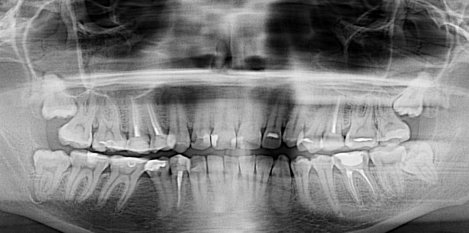

Мне 21 год. Год назад мне поставили химическую пломбу на 24 зуб. Пломба частично вывалилась, и как бы внутри зуба образовалась дырка, в которую постоянно попадала еда и гнила там. Через несколько месяцев я поставила новую пломбу, тоже химическую. Но возникла снова та же проблема.

Недавно я обращалась в несколько стоматологий. Мне сказали, что в зубе развивается кариес, и стенки его тонкие. Одни предлагали поставить штифт и новую светоотвердевающую пломбу. Другие говорили, что необходим штифт и коронка.